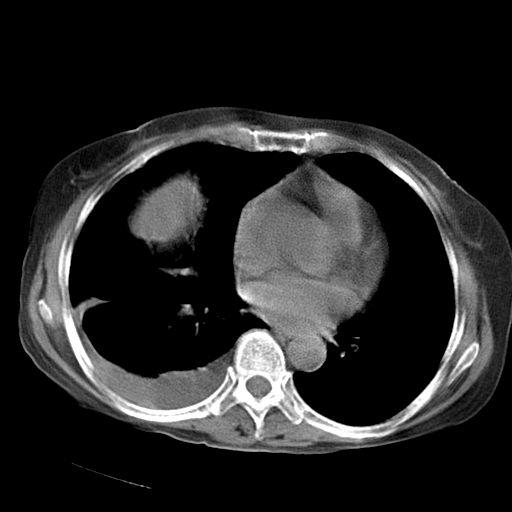

以下是引用jiazh在2006-12-7 20:37:00的发言:[br]肝脏周围半狐形低密度影,肝脏表面受压推移,考虑膈下脓肿可能性大;2、右侧胸腔积液

以下是引用拾荒者在2006-12-7 21:44:00的发言:[br]肝内外胆管多发结石,右膈下多发脓肿,右胸膜腔及叶间裂积液,左肾囊肿。[br] [br]